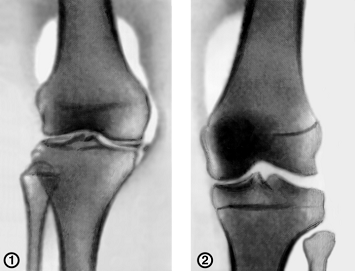

Рис.5.

Пневмоартрография коленного сустава в прямой проекции.

На

рис. 5 показан пример пневмоартрографии коленного сустава в прямой проекции : 1

- вертикальный отрыв внутреннего мениска в паракапсулярной области. Над

медиальным мыщелковым бугорком межмыщелкового возвышения большеберцовой кости

выявляется внутрисуставное тело; 2 - сустав в норме.